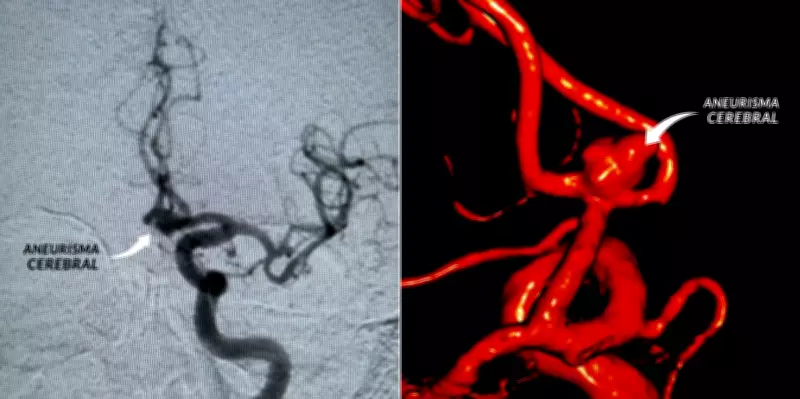

Um aneurisma cerebral é definido como uma dilatação localizada na parede de uma artéria. Essa dilatação estica a parede do vaso sanguíneo, deixando-a enfraquecida e formando uma espécie de bolsa, que pode se romper a qualquer momento, conforme explicações do neurocirurgião Helder Picarelli, pós-doutor pela Universidade de São Paulo (USP).

No cérebro, esses pontos frágeis costumam surgir principalmente nas bifurcações das artérias. Muitas vezes, o aneurisma não provoca sintomas perceptíveis até que ocorra a ruptura, o que torna a condição especialmente perigosa e silenciosa.